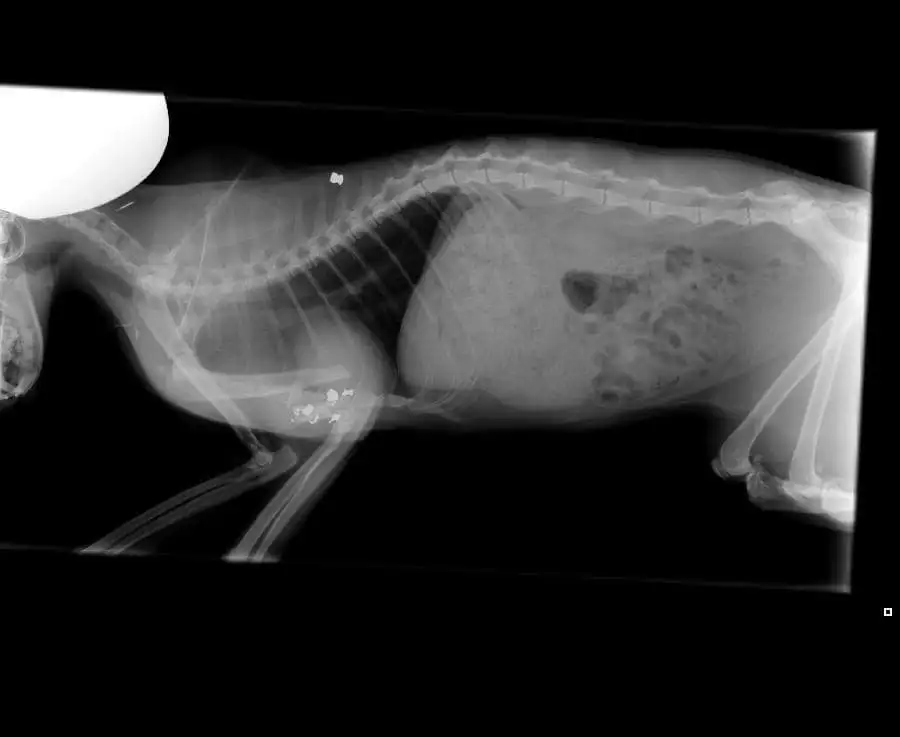

"Zaterdagmorgen wilde ik met mijn kinderen weggaan en toen ik deur opendeed, hoorde ik ineens gemiauw." Bumba ligt onder de glijbaan van de kinderen en kan nauwelijks lopen. Samantha belt de dierenarts. De kat krijgt pijnstillers, maar het helpt weinig. Als Samantha weer bij de dierenarts aanklopt, worden er röntgenfoto's gemaakt. "De dierenarts zei bij het zien van de foto's meteen dat ze was mishandeld. De kogels hebben letterlijk het bot in haar pootje door midden gemaakt." Alleen de huid houdt het pootje en de rest van het lichaam nog bij elkaar. Amputatie is de enige optie.